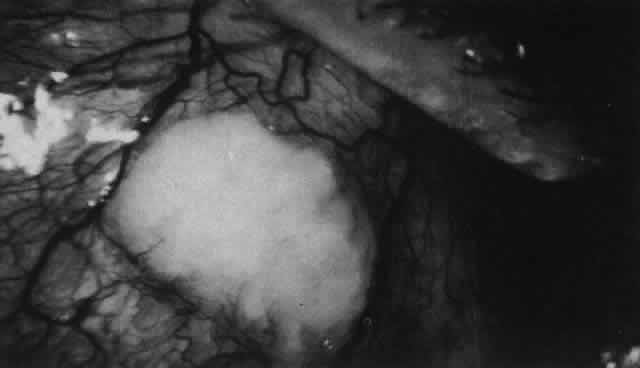

Scleritis usually affects the anterior segment of the eye, possibly because this is the area with the best blood supply, but with sluggish flow through the vessels (Fig. 19). The sclera is thickened and roughened in the affected area, which appears to be sharply demarcated from the rest of the sclera. However, tissue obtained at surgery during the course of grafting of areas adjacent to necrotic tissue shows marked pathologic changes.20,21 The area of affected sclera may be swollen, excavated, or frankly ulcerated with undermined edges covered with a thin layer of fibrous tissue. However, spontaneous perforation is extremely unusual and, where seen in pathologic specimens, has usually occurred at the time of removal of the eye. A posterior scleritis often occurs as an extension of anterior disease; but, as in Figure 20, most of the inflammation (in some cases all of the inflammation) is in the posterior segment and the exudative detachments and subretinal granulomas can be mistaken for malignant melanoma.

Fig. 19. Anterior necrotizing scleritis. The eye was removed because of loss of vision and intractable pain. No form of steroid was given to this patient because of a severe Pseudomonas infection of the chest. (Courtesy of Professor N. Ashton)

Fig. 20. Posterior scleritis. This eye was removed because of loss of vision and pain, mistakenly diagnosed as malignant melanoma. (Courtesy of Professor N. Ashton)